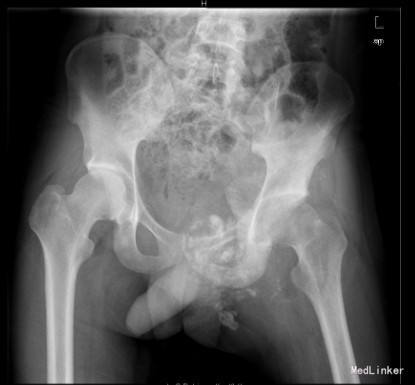

患者男,22岁,因“左臀部包块伴疼痛,进行性增大8+月”入院。入院前8+月,患者无明显诱因出现左臀部疼痛,并发现局部有包块。疼痛为钝痛,坐时加重,常反复,不伴发热及盗汗。于当地医院就诊,怀疑骨盆肿瘤;现为求进一步诊疗来我院就诊。

查体:左侧臀部内侧区隆起,局部皮肤无充血红肿,无浅静脉怒张,无皮肤破溃、皮疹及足癣。左侧臀部内侧区及左侧腹股沟区可触及巨大圆形包块,质硬,压痛明显,皮温不高,无明显触觉减退区,左足背动脉搏动正常,肢端末梢血循环正常。 辅查:骨盆CT提示左髂骨恶性肿瘤,突破皮质,边界不清,部分钙化。

初步诊断:左侧骨盆骨肉瘤(Ⅰ+Ⅱ+Ⅲ区) 诊疗计划:完善术前抽血常规、心电图及胸片等检查后择期手术治疗。